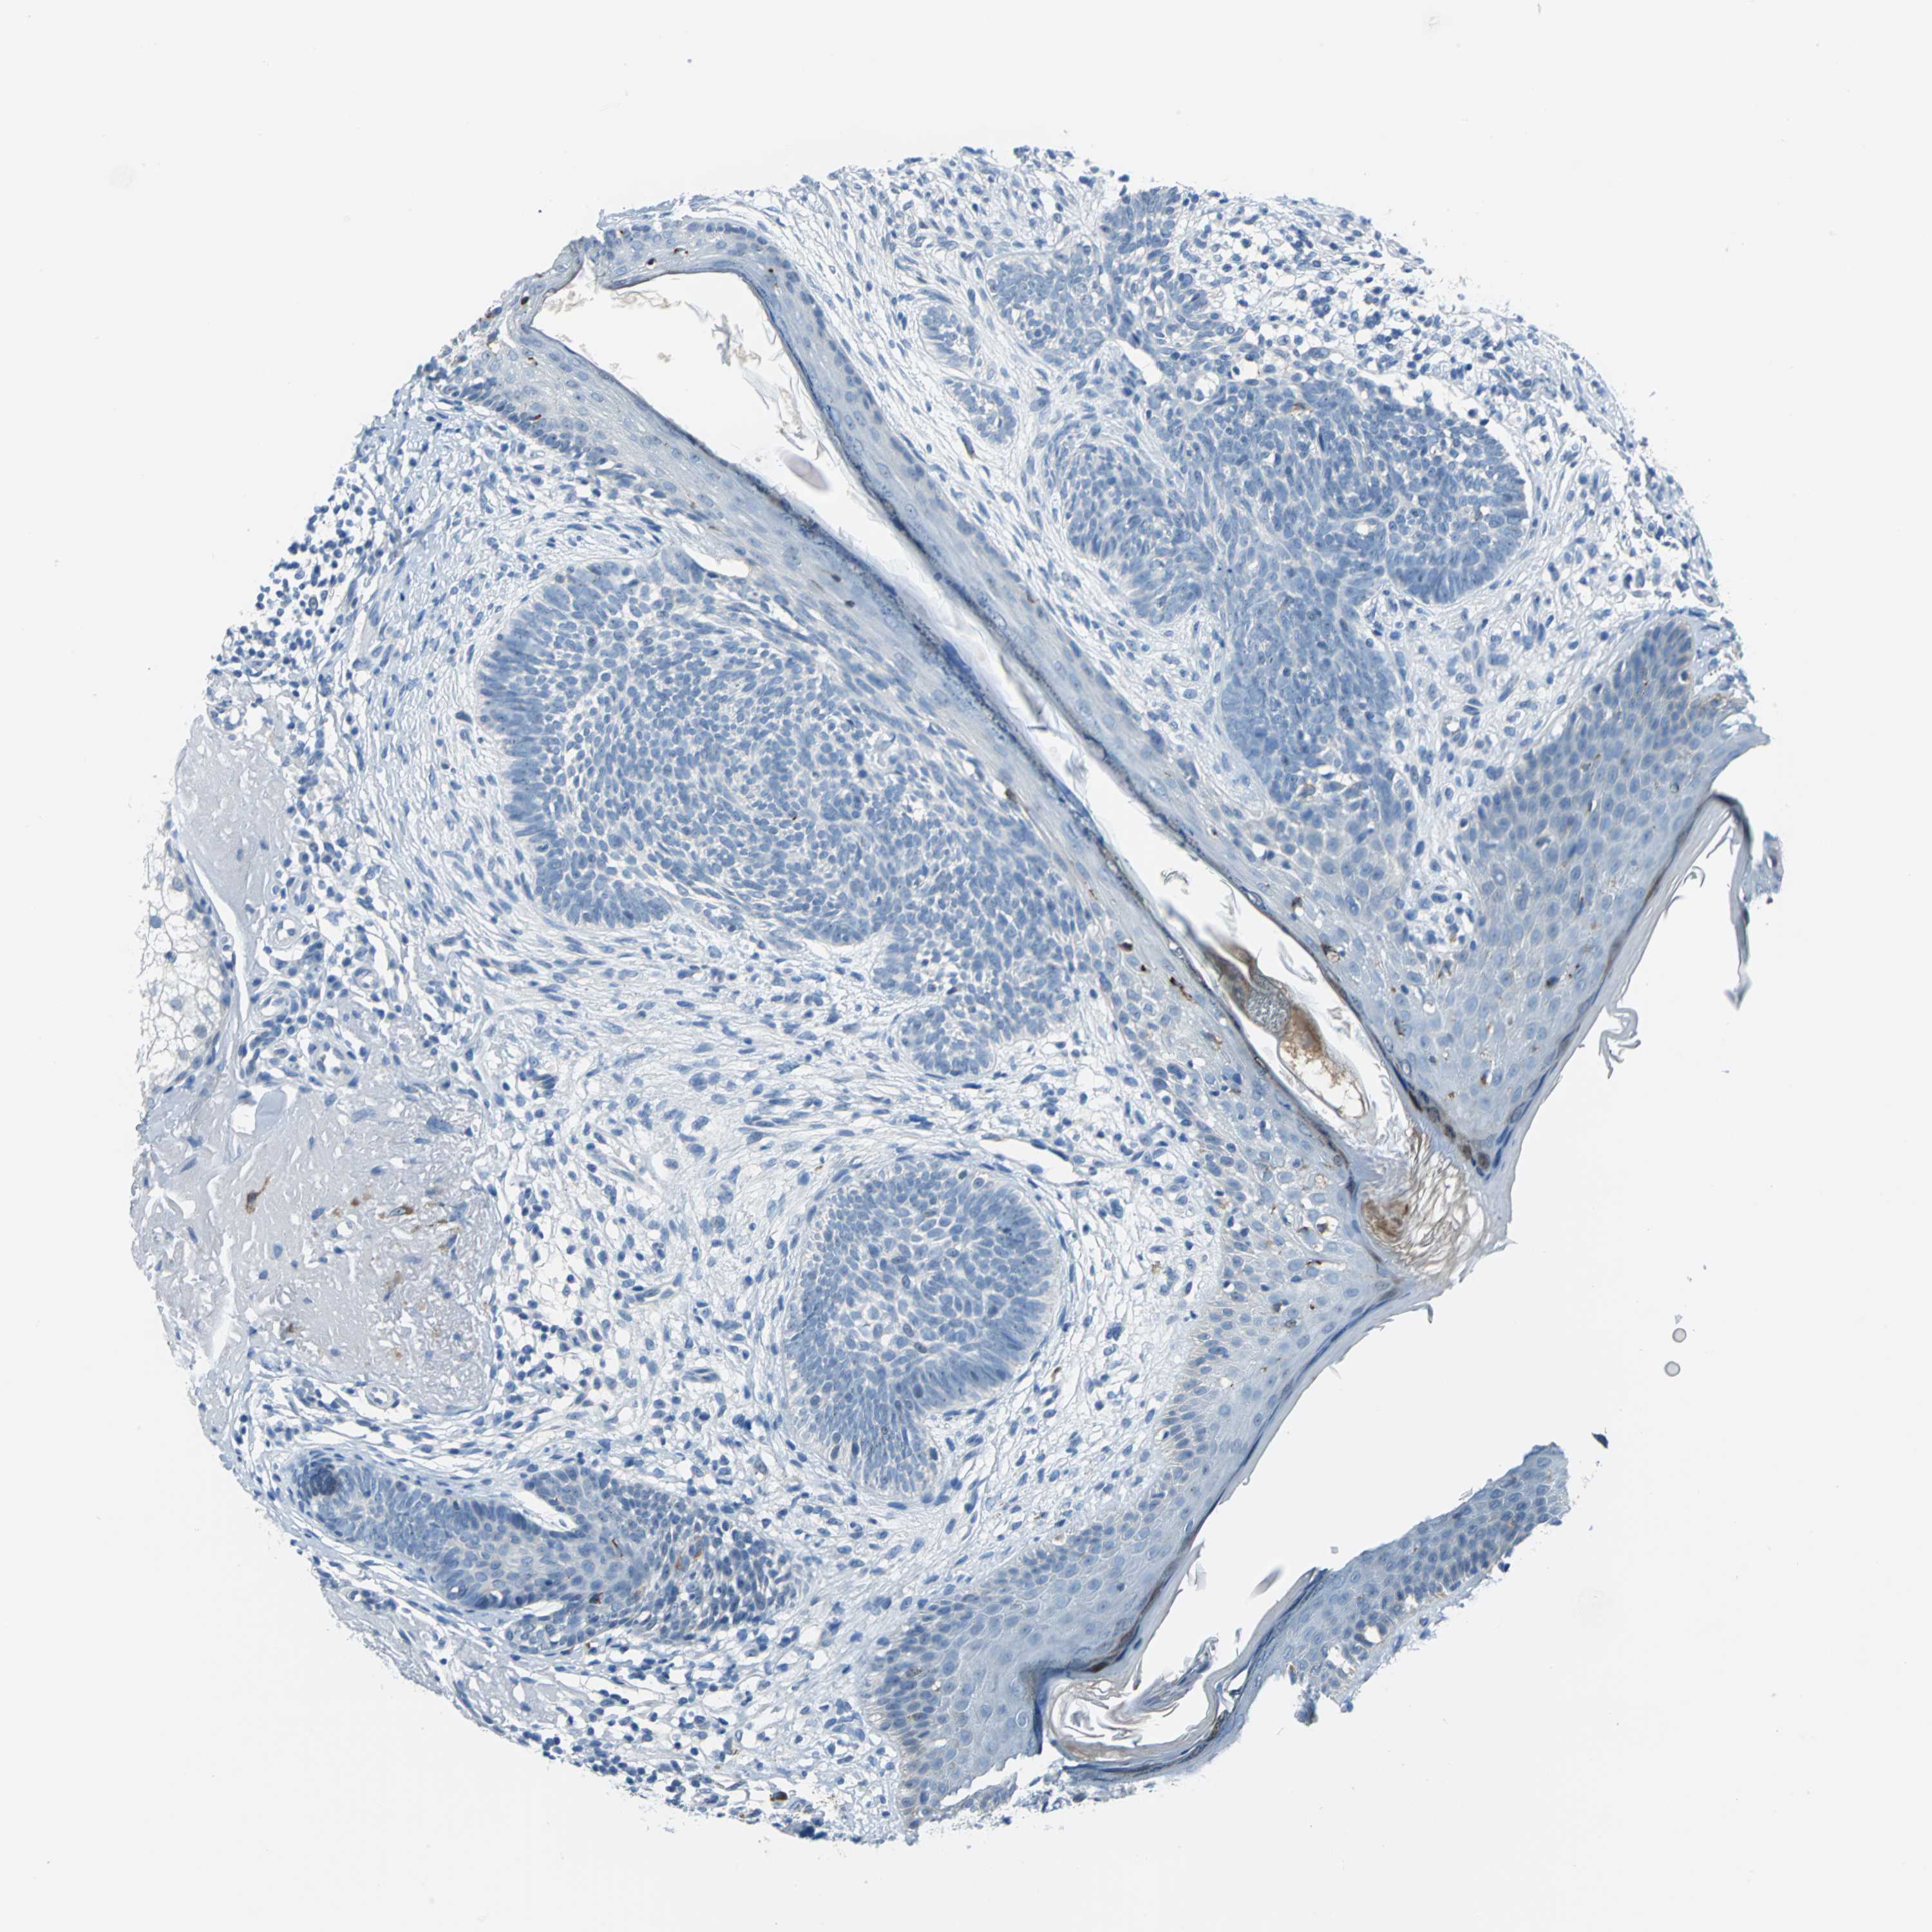

SKIN CANCER - Protein expressioni

A mouse-over function shows sample information and annotation data. Click on an image to view it in a full screen mode. Samples can be filtered based on level of antibody staining by selecting one or several of the following categories: high, medium, low and not detected. The assay and annotation is described here.

Antibody stainingi

Antibody staining in the annotated cell types in the current human tissue is reported as not detected, low, medium, or high, based on conventional immunohistochemistry profiling in selected tissues. This score is based on the combination of the staining intensity and fraction of stained cells.

Each image is clickable and will lead to virtual microscopy that enables deeper exploration of all samples and also displays staining intensity scores, fraction scores and subcellular localization as well as patient and tissue information for each sample.

Antibody HPA005895

Antibody CAB013536

Squamous cell carcinoma, NOS

Basal cell carcinoma